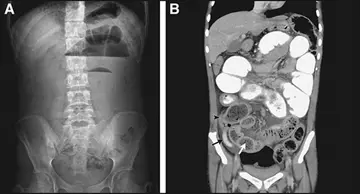

ولـوولـوس روده کوچـک

یک مرد 67 ساله با درد حاد شکم که از 3‌ساعت پیش شروع شده بود به بخش اورژانس مراجعه کرد.